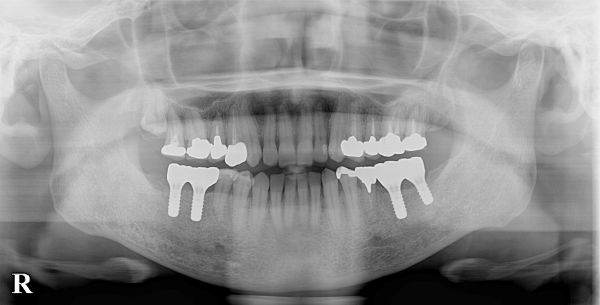

こちらが初診時のレントゲン写真となります。

左下6・7番目の歯が抜歯をされ、欠損している状態でした。

こちらが被せ物が入った後のレントゲン写真になります。